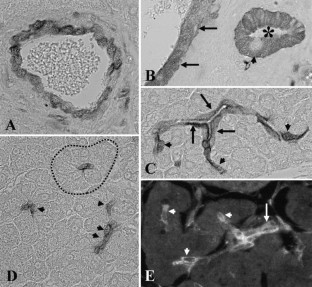

Fig. 1A–D

Fig. 2A–D

Fig. 3

Fig. 4A–H